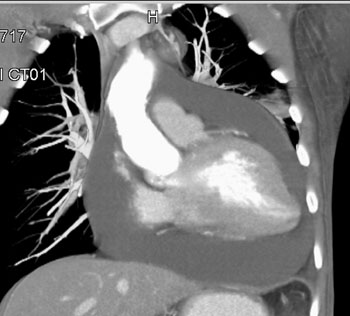

Question 5: 47 year old male with mass discovered on CT during chest pain workup. What is the diagnosis?

Diagnosis: Pericardial cyst

• Smoothly marginated lesion surface

• Less than 10 HU

• No enhancement on contrast studies

• Size range from 2-30 cm

• Usually at right anterior costophrenic angle

• Water density on CT

• 2-30 cm in size

• Homogeneous without any enhancement